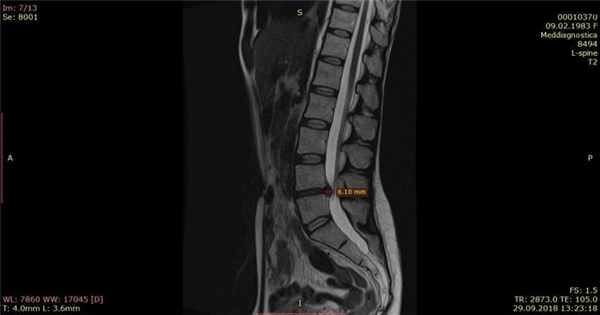

Оценив исходные данные (результаты анализов, биомеханику позвоночника и др.) мы приступили к «высушиванию» и «вправлению» грыжи диска. По прошествии 1 месяца грыжа уменьшилась на 50%.

Контрольный МРТ, через 5 месяцев показал полное отсутствие грыжи диска (см. снимки Ирины ниже):

Обратите внимание на даты проведения МРТ в правом нижнем углу. МРТ исследования проведены на одном аппарате 1.5 теслы в клинике «Меддиагностика» в процессе лечения Ирины. МРТ позвоночника позволяет отследить динамику уменьшения грыжи диска.